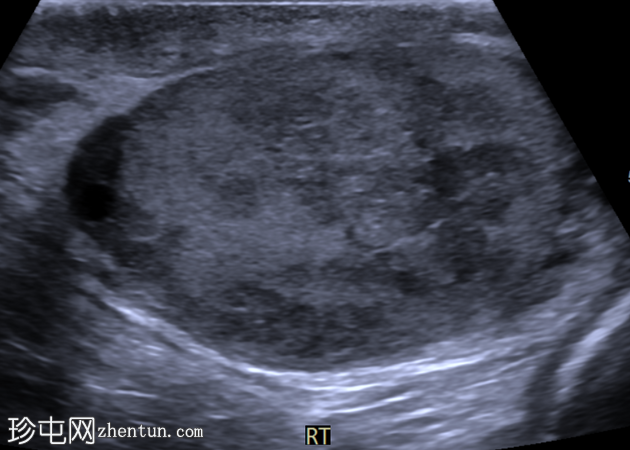

右侧睾丸内可见一大小约3.0 x 5.0 cm的异质性分叶状低回声肿块。肿块内未见囊性区域或钙化。彩色多普勒超声检查显示肿块内血流丰富。左侧睾丸正常。